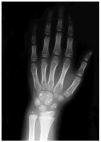

Un estudio radiológico de serie ósea identificó numerosas lesiones esclerosas redondeadas, de bordes bien definidos, localizadas en metatarso, metacarpo, falanges (fig. 3) y epífisis de tibia y peroné, sin afectación cortical, compatibles con lesiones de osteopoiquilia. Los padres del paciente no mostraban alteraciones cutáneas y no se han realizado estudios radiológicos.

Fig. 3.--Lesiones osteoscleróticas en el carpo, metacarpo y falanges.